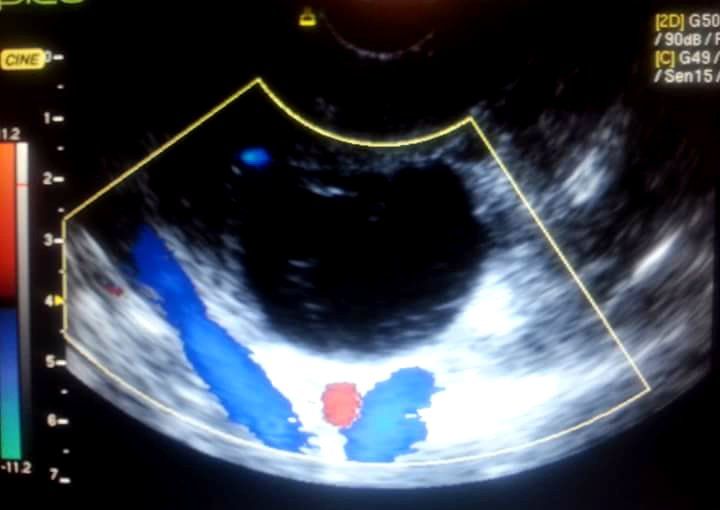

ECODOPPLER FETAL

Vitalidad fetal, valoración de la forma de onda de la velocidad de flujo del cordón umbilical , (presencia de tres vasos, a saber :dos arterias y una vena), la placenta (madurez) y evaluación de las arterias uterinas.(oportuna disminución en el Índice de resistencia a partir la oleada de invasión trofoblástica)

Valoración de la cantidad de líquido amniótico (Índice de líquido amniótico I.L.A) y su calidad.

Sirve para medir y evaluar el flujo de sangre que recibe el bebé a través del cordón umbilical, así como también su correcta distribución en el interior de su organismo.

Es muy útil ante la sospecha de retraso de crecimiento fetal (R.C.I.U), como así también en embarazos complicados con hipertensión materna, diabetes, trombofilias y diagnósticos más complejos, por ejemplo, en embarazos gemelares mono amnióticos, el diagnóstico de síndrome de feto transfusor-transfundido).

Diagnóstico oportuno de sufrimiento fetal.